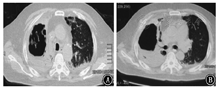

患者短期内双肺出现散在斑片影及斑点影,伴大小不等空洞,考虑肺部感染性疾病。入院后给予比阿培南(0.6 g,静脉滴注,2次/d)+万古霉素(0.5 g,静脉滴注,每8小时1次)联合抗细菌,继续醋酸泼尼松40 mg/d口服抗炎,并给予多索茶碱静脉滴注、雾化吸入布地奈德及特布他林平喘,氨溴索静脉滴注化痰,皮下注射胰岛素控制血糖等治疗。完善相关检查,ESR为47 mm/h;C反应蛋白96.10 mg/L;生化:钾4.0 mmol/L,钠131.0 mmol/L,氯96.0 mmol/L,空腹血糖17.0 mmol/L,尿素7.1 mmol/L,肌酐68.0 μmol/L,丙氨酸氨基转移酶29.0 U/L,天门冬氨酸氨基转移酶13.0 U/L,乳酸脱氢酶253 U/L,肌酸激酶79 U/L,总蛋白51.1 g/L,白蛋白30.8 g/L。尿常规:葡萄糖++++;血结核菌38kD蛋白阴性,结核菌外膜抗体阳性;结核菌素试验阴性;降钙素原、抗链球菌O、类风湿因子、自身抗体系列、肿瘤相关抗原系列、粪常规均正常。术前四项(乙肝表面抗原、丙肝抗体、人类免疫缺陷病毒抗体、梅毒血清特异性抗体)阴性。心电图大致正常。心脏超声:主动脉瓣钙化,左室后壁运动幅度稍减低,左室舒张功能减低。腹部超声:脂肪肝,余未见异常。肺功能:第1秒用力呼气容积/FVC为43.22%,第1秒用力呼气容积占预计值百分比为24.9%,提示阻塞性通气功能障碍,小气道功能障碍,残气量/肺总量轻度增高,弥散功能重度减低。痰涂片找抗酸杆菌阴性(3次)。患者入院当日(2018年1月26日)发热,最高体温达38 ℃;1月27日体温正常;1月28日再次发热,最高体温达38.1 ℃;1月29日之后未再发热,憋喘较前略好转,痰中带血减少。1月29日痰涂片:革兰阳性球菌可见;痰真菌培养:白色假丝酵母菌+。1月30日血1,3-β-D葡聚糖检测(G试验):247.3 μg/L(升高);血常规:白细胞计数12.56×109/L,红细胞计数5.00×1012/L,血红蛋白143 g/L,血小板计数179×109/L,中性粒细胞比例85.3%,淋巴细胞比例7.6%;C反应蛋白55.10 mg/L;血气分析:pH值7.43,PaCO2为48.4 mmHg,PaO2为81.6 mmHg,SaO2为95.8%。入院后每日皮下注射胰岛素累积剂量56 IU。1月26日至1月30日血糖控制不理想,空腹血糖波动于11~18 mmol/L,早餐及午餐后2 h血糖波动于10~18 mmol/L,晚餐后2 h血糖波动于15~21 mmol/L。患者痰检见白色假丝酵母菌+,G试验轻度增高(近期有应用哌拉西林舒巴坦钠史,不排除干扰),近期有糖皮质激素应用史,血糖控制欠佳,综合以上因素,考虑肺真菌感染不排除。1月30日给予伏立康唑200 mg口服抗真菌,每12小时1次(第1个24小时400 mg/次),同时减量醋酸泼尼松为30 mg/d。2月2日痰真菌培养:曲霉菌属+(2次),白色假丝酵母菌+,进一步支持真菌感染,建议行气管镜检查,患者因喘憋不适,一直不同意。之后又有2次痰培养:曲霉菌属1~2个菌落。2月5日患者憋喘较重,复查血常规:白细胞计数23.32×109/L,红细胞计数5.22×1012/L,血红蛋白151 g/L,血小板计数208×109/L,中性粒细胞比例92.2%,淋巴细胞比例3.7%;C反应蛋白229.80 mg/L;血气分析:pH值7.44,PaCO2为47.3 mmHg,PaO2为82.3 mmHg,SaO2为95.7%,提示感染加重。2月5日伏立康唑改为0.3 g,静脉滴注,每12小时1次。2月6日胸部CT示双肺散在斑片影及斑点影,伴大小不等空洞,与1月26日胸部CT比较右肺上叶空洞增大,右肺上叶病变进展(图3)。继续伏立康唑静脉滴注抗真菌,比阿培南联合万古霉素抗细菌治疗。2月12日胸部CT示右肺上叶空洞较2月6日进一步增大(图4)。2月12日血气分析:pH值7.45,PaCO2为57.2 mmHg,PaO2为78.3 mmHg,SaO2为95.1%。经反复动员,2月13日患者同意气管镜检查,结果(图5)示主气管黏膜表面可见白色分泌物附着;左上叶支气管黏膜充血明显,可见大量脓性分泌物;右上叶支气管各叶段开口变窄,以右上叶尖段开口变窄明显;右上叶支气管黏膜充血水肿明显,活检或刷检易出血。气管镜刷片及灌洗液病理见少许坏死物及中性粒细胞,未见肿瘤细胞。支气管镜肺活检(右上叶)病理:送检肺组织慢性炎,肺间质可见单核细胞浸润,纤维组织增生,肺泡上皮增生,肺组织表面附着成团的坏死物,坏死物中可见真菌菌丝及孢子。气管镜刷片培养:曲霉菌属1个菌落;气管镜后痰培养:曲霉菌属4个菌落。患者IPA诊断依据充足,应用伏立康唑效果差,2月14日改为两性霉素B脂质体静脉滴注,从10 mg/d始,逐日递增,增至150 mg/d时患者精神萎靡、憋喘、乏力、纳差、尿少、肾功能异常,尿素18.5 mmol/L,肌酐166 μmol/L,总蛋白45.6 g/L,白蛋白26.9 g/L。2月18日血气分析:pH值7.38,PaCO2为55.4 mmHg,PaO2为72.4 mmHg,SaO2为93.5%。考虑患者对该药不良反应较大,停用两性霉素B脂质体。2月19日给予伏立康唑(0.3 g,静脉滴注,每12小时1次)联合卡泊芬净(50 mg/d,静脉滴注)抗曲霉菌治疗。2月20日后患者多次血气分析示PaCO2升高,波动于56~79 mmHg,PaO2低,波动于50~80 mmHg,给予保肾、人血白蛋白支持、无创呼吸机辅助通气等治疗。口服泼尼松经逐渐减量,于2月17日后停用。住院期间患者一直纳差,进食量少,尽管每日皮下注射胰岛素累积剂量60 IU,但血糖仍控制不理想,空腹血糖波动于12~20 mmol/L,餐后2 h血糖波动于14~26 mmol/L;自停用泼尼松后,血糖逐渐好转,空腹血糖波动于8~10 mmol/L,餐后2 h血糖波动于11~14 mmol/L。3月6日血气分析:pH值7.35,PaCO2为55.4 mmHg,PaO2为72.4 mmHg,SaO2为93.5%。3月6日胸部CT示双肺多发空洞,右肺上叶空洞较前增大,双肺病变继续进展(图6)。治疗效果不理想,家属要求转院。